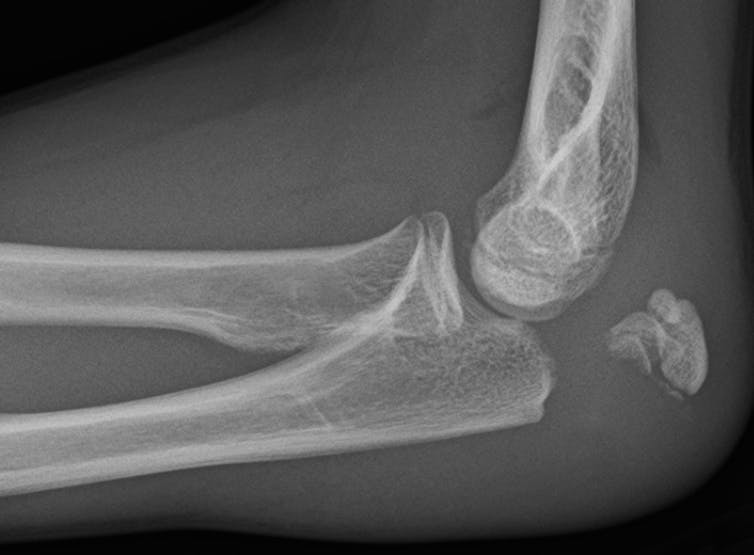

When you get an MRI or an X-ray, having a radiologist interpret the results is often the most costly and time-consuming part of the process. The potential to speed up interpretation of results and cut costs has led many hospitals to contract with separate, off-site radiology services.

The practice is widespread: About 50% of radiologists say that they have interpreted imaging results away from where the images were taken and a quarter say that off-site interpretation is the majority of their work.

For smaller and rural health care systems that lack the resources to staff in-house radiologists, outsourcing may be essential. But for larger health care systems, outsourcing can sometimes lead to negative clinical and business consequences that outweigh the benefits.

For instance, off-site radiologists often lack access to patients’ prior imaging records or medical history. If these radiologists can’t see how a person’s condition has changed over time, it is harder to make an accurate diagnosis. This can lead to unnecessary and costly further testing. Moreover, off-site radiologists can have a harder time communicating with the physician who ordered the test, potentially reducing the quality and continuity of care.